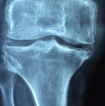

겨드랑이 통증 원인 2. 관절염

겨드랑이 주변 관절에 염증이 발생하는 경우, 관절염으로 인한 통증이 발생할 수 있습니다.